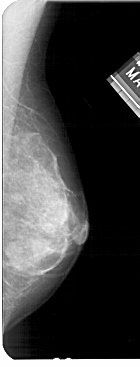

A_1475_1.RIGHT_MLO

RIGHT_CC LINES 3886 PIXELS_PER_LINE 1846 BITS_PER_PIXEL 12 RESOLUTION 43.5 NON_OVERLAY

RIGHT_MLO LINES 5491 PIXELS_PER_LINE 2086 BITS_PER_PIXEL 12 RESOLUTION 43.5 NON_OVERLAY